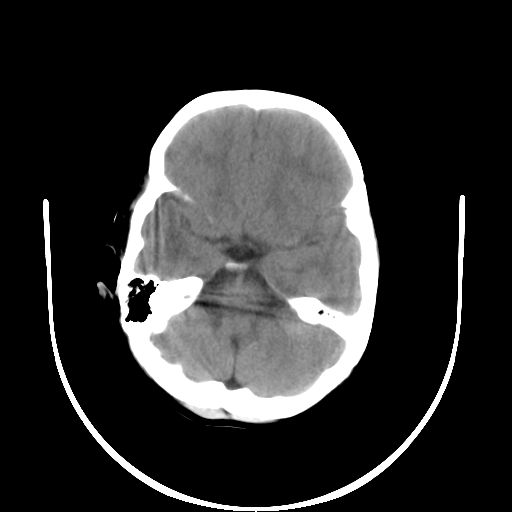

以下是引用深泽交通医院在2009-10-16 8:25:00的发言:[br]右眼环出血伴异物

以下是引用卜一在2009-10-16 15:01:00的发言:[br]右眼球挫裂伤伴异物!

以下是引用拾荒者在2009-10-17 18:38:00的发言:[br]鼻面部皮下积气,右侧睑缘及眼球壁高密度异物影,左侧眼球壁晶状体内侧缘处是圆形低密度影。低密度异物?应提请眼科医生注意。